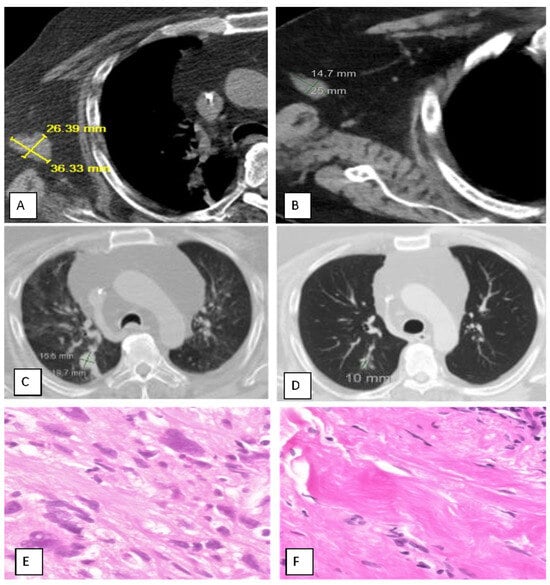

Background/Objectives: Little is known about the synergy between intratumoral immunotherapy and cancer ablation. We conducted a Phase II Trial (Abscopal 5001 trial; NCT04713371) in patients with metastatic solid cancer to assess the safety and efficacy of cryoablation with concurrent injection of RPT-01-5001 (combination of low-dose checkpoint inhibitors and cyclophosphamide), a treatment process referred to as Multiplex Intratumoral Immunotherapy (MITITM). Methods: Twelve patients with metastatic cancer who had failed standard therapy and one with sacral chordoma received at least one intratumoral treatment of MITI preceded by 3–5 days of oral low-dose cyclophosphamide. MITI consisted of CT-guided cryoablation followed by intratumoral injection of RPT-01-5001. GM-CSF was subcutaneously administered daily for four weeks. Treatment was repeated every four weeks if the tumor burden remained stable or reduced, as noted by the iRECIST criteria. These criteria were modified when follow-up biopsies revealed pathology with minimal or no cancer, despite persistent suspicious masses on imaging. Results: Cancers included prostate (four patients), sarcoma (two), and one each of breast, colon, bladder, uterine cervix, tongue, kidney, and sacral chordoma. Eight patients received three cycles of treatment, two received two, and three received one. All patients tolerated the procedure well and were discharged within 2 h. The adverse event rate was 69%, all of which were grade 1 or 2, except for two grade 3 cases with delayed cryosurgical complications (15%). At completion of up to three cycles of treatment, a complete response (iCR) was observed in one patient (7.7%), partial response (iPR) in four patients (30.8%), and stable disease (iSD) in five (38.5%), with a disease control rate (iDCR) of 77%. Disparity between post-treatment imaging and pathologic findings was observed in four patients (positive vs. negative, respectively), requiring modification of the iRECIST criteria in favor of pathology. The best response ranged from 0 to 91%, with a mean for responding patients of 38%. Median progression-free survival (PFS) and 95% confidence intervals (95% CI) were 5.4 months (1.8 to 23.1 months); and median overall survival (OS) was 20.9 months (9.1 to 22.8 months). The injection site cancer response was observed in nine (69%) patients, and the distal abscopal effect was seen in four (31%), including one sarcoma patient with a complete abscopal response of lung metastases and one bladder cancer patient with biopsy-confirmed complete resolution of lung and liver metastases. Conclusions: MITI with RPT-01-5001 is safe and highly feasible, providing 77% disease control and 31% of the abscopal effect in patients with metastatic cancer who have failed standard therapies. Full article